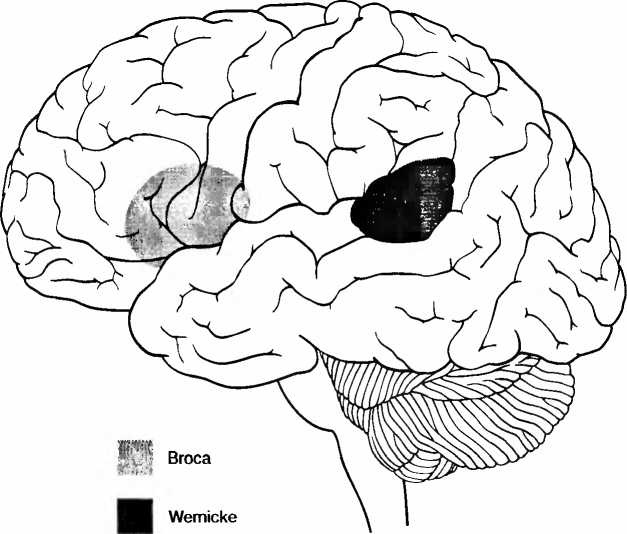

Иллюстрация к книге — Мы - это наш мозг. От матки до Альцгеймера [i_010.jpg]

Рис. 7. Речевые центры Брока (лобный, владение речью) и Вернике (височный, понимание речи). Эти центры также тесно связаны с восприятием музыки и пения. Музыка и речь очень близки друг к другу.